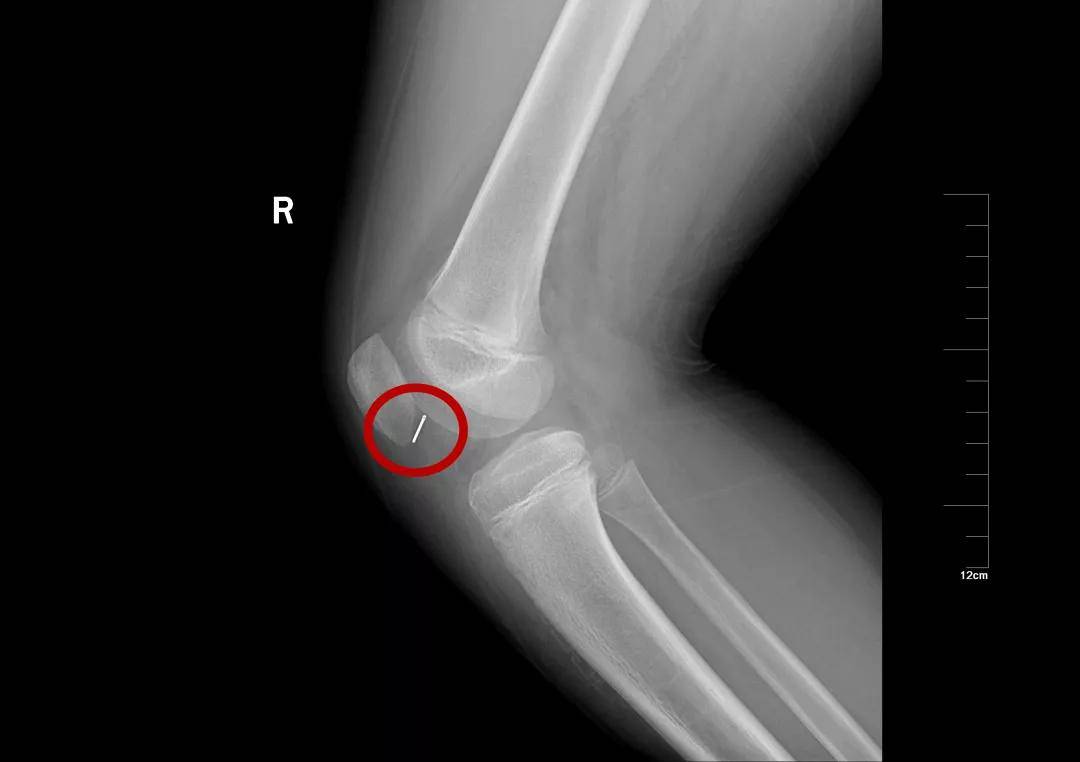

10岁·膝盖异物

半截针

患儿10天前不慎受伤,致半截床套针刺入右膝,无明显疼痛及活动障碍,至当地医院就诊摄片示右膝异物。